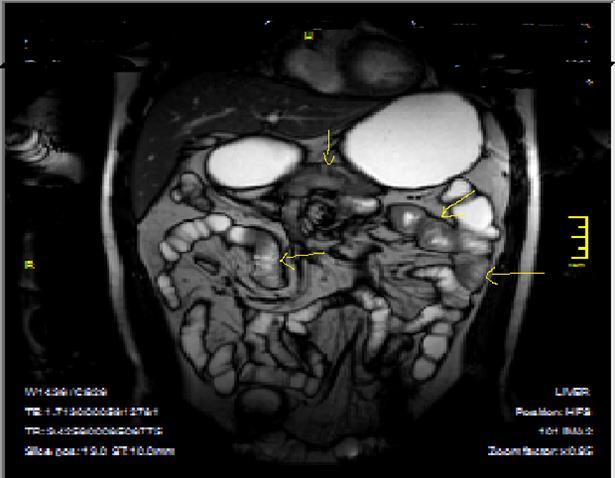

Pathognomonic signs of Crohn’s disease are; Bowel wall thickness must be higher than 2 mm in small intestine, 3 mm in colon, valvula conniventes has to be less than 3 mm, and small intestine diameter will be less than 3 cm, long segment intestinal infiltration, creeping fat sign, loss of haustration in colonic segments, skip lesions between normal and diseased segments and transmural invasion of bowel wall2, 5, 12, 14,18, 19, 20. In endoscopy; Aftos ulcerations and erosions are found out initially in the normal bowel mucosa than at later stages, mural stratification with longitudinal and transverse ulcerations are observed7, 14, 20, 21. On MRI; High bowel wall enhancement is particular at active inflammation, increased signal at bowel wall and adjacent mesentery on T2W images, strictures-fistulization and abcesses are the main complications and hyperintense on T2W images, asymmetrically thickened mucosal folds and lymphadenopathy, mesenteric stranding of the effected bowel wall and prominent draining vessels of the inflamed intestinal loops(comb sign), presence of intramural fat at chronic phase and target sign due to wall thickening at acute phase, surrounding peri-intestinal edema in acute phase are the main findings of Crohn’s disease7, 12, 14,18, 19, 20, 21 (Figure 2a-b)

Figure 2a.Concentric luminal narrowing, mural and transmural involvement of terminal ileum due to Crohn’s disease in T2W coronal sequence after OCA application.

Figure 2b.Curvi-lineer, diffuse peripheral enhancing bowel wall in the terminal ileum on axial T1W post-contrast image.